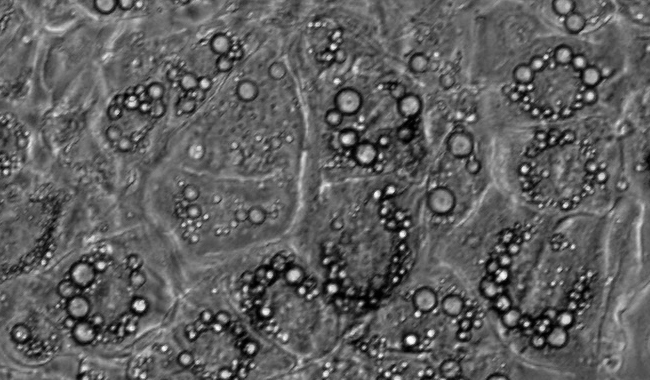

脂滴計數圖像分析

脂滴是調節中性脂質儲存的基礎,可以根據脂滴研究代謝的需求。但它們不僅是能量庫,因為這種動態的細胞器是許多生物過程的一部分,如細胞能量平衡和脂質代謝。脂滴法在代謝性疾病的研究,如肥胖、糖尿病和動脈粥樣硬化有重要的作用。

脂滴個數

脂滴覆蓋面積

平均覆蓋面積

區間分布

單個細胞的脂滴個數和覆蓋面積